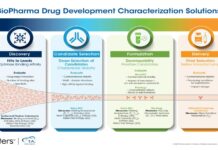

Validated through an industry recognised third party and validated against the Comprehensive in vitro Pro-arrhythmia Assay (CiPA) guidelines, Axol’s Human iPSC-derived Atrial Cardiomyocytes express typical targets, ion channels and currents (Kv1.5, Ikir3.x, Ikur, IKACh, MLC2a & ANP) essential for the screening of cross target effects, the development of atrial specific target drugs, and the investigation of atrial fibrillation and inherited cardiac conditions. The overall potential and application of the Human iPSC-derived Atrial Cardiomyocytes can be enriched when cultured with Axol’s serum-free Cardiomyocyte Maintenance Medium, reducing variability and enhancing consistency in their culture.